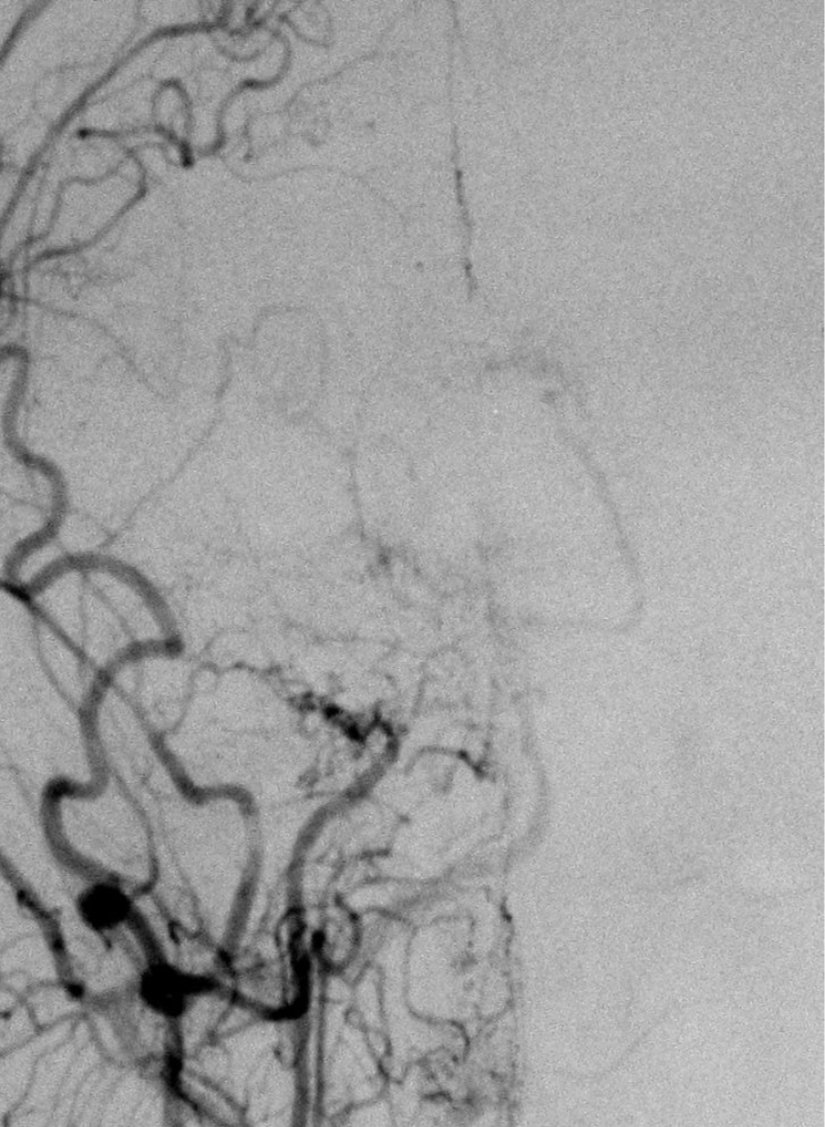

Moyamoya hastalığının teşhisi, nadir görülmesi ve bariz olmayan belirti ve semptomlardan dolayı zor olabilir. Teşhis, klinik bulgular ve görüntüleme bulguları temelinde şüphelenilerek konur. Teşhisin doğrulanması için standart yöntem serebral anjiyografi olarak kabul edilir.[7]

Serebral anjiyografi, moyamoya hastalığını doğrulamak için kullanılan standart bir yöntemdir. İşlem sırasında, kontrast madde enjeksiyonu ile beyin damarlarının röntgen filmi çekilir. Ancak, bu yöntem intravenöz kontrast kullanımına bağlı alerjik reaksiyonlar ve nadiren kontrast maddeye bağlı böbrek hasarı gibi riskleri içerebilir.[7]

Japonca'da "havada dağılan sigara dumanı" anlamına gelen ve "moyamoya" şeklinde telaffuz edilen "もやもや" terimi, hastalığın anjiyografik görünümünden esinlenmiştir.[1], [2], [5], [8]